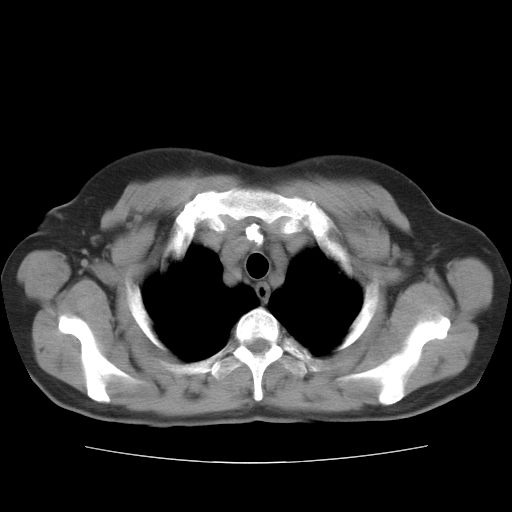

标题: CT10838:女性,56岁,是上腔静脉钙化还是淋巴结钙化? [打印本页]

标题: CT10838:女性,56岁,是上腔静脉钙化还是淋巴结钙化?

女性,56岁临床诊断为胃贲门ca,术前检查发现,此钙化灶,对此科内稍有争论!请各位老师看看!是上腔的还是淋巴结的?有意义吗?

胸锁关节层面的是淋巴结钙化,气管前腔静脉后的钙化灶占了4个层面,不知层厚是多少?看样子应该是7--10毫米之间,那么这病灶最小纵径得有28毫米!应该提示点什么了,没传肺窗,估计肺内没有病变?

左锁骨下静脉和头臂静脉会合后形成是上腔静脉,此钙化位于两血管回合的腔静脉后方、气管右前方,这个位置没有其他结构,应该是淋巴结钙化。一般多为淋巴结核后钙化,没有临床意义。